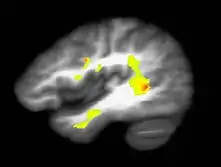

According to some reports, prolonged cannabis use (now termed CUD) causes decreased reactivity to dopamine, suggesting a possible link to an inhibited reward system and an increased addiction of severity.[16] Cannabis use disorder is now defined in the fifth revision of the Diagnostic and Statistical Manual of Mental Disorders, the main authoritative guide for mental health disorders in Australia.[11]

Recent research has indicated that adolescent cannabis use is associated with increased misuse as an adult, as well as long-term cognitive implications and psychiatric problems.[17] This may be because the endocannabinoid system is directly involved in adolescent brain development.